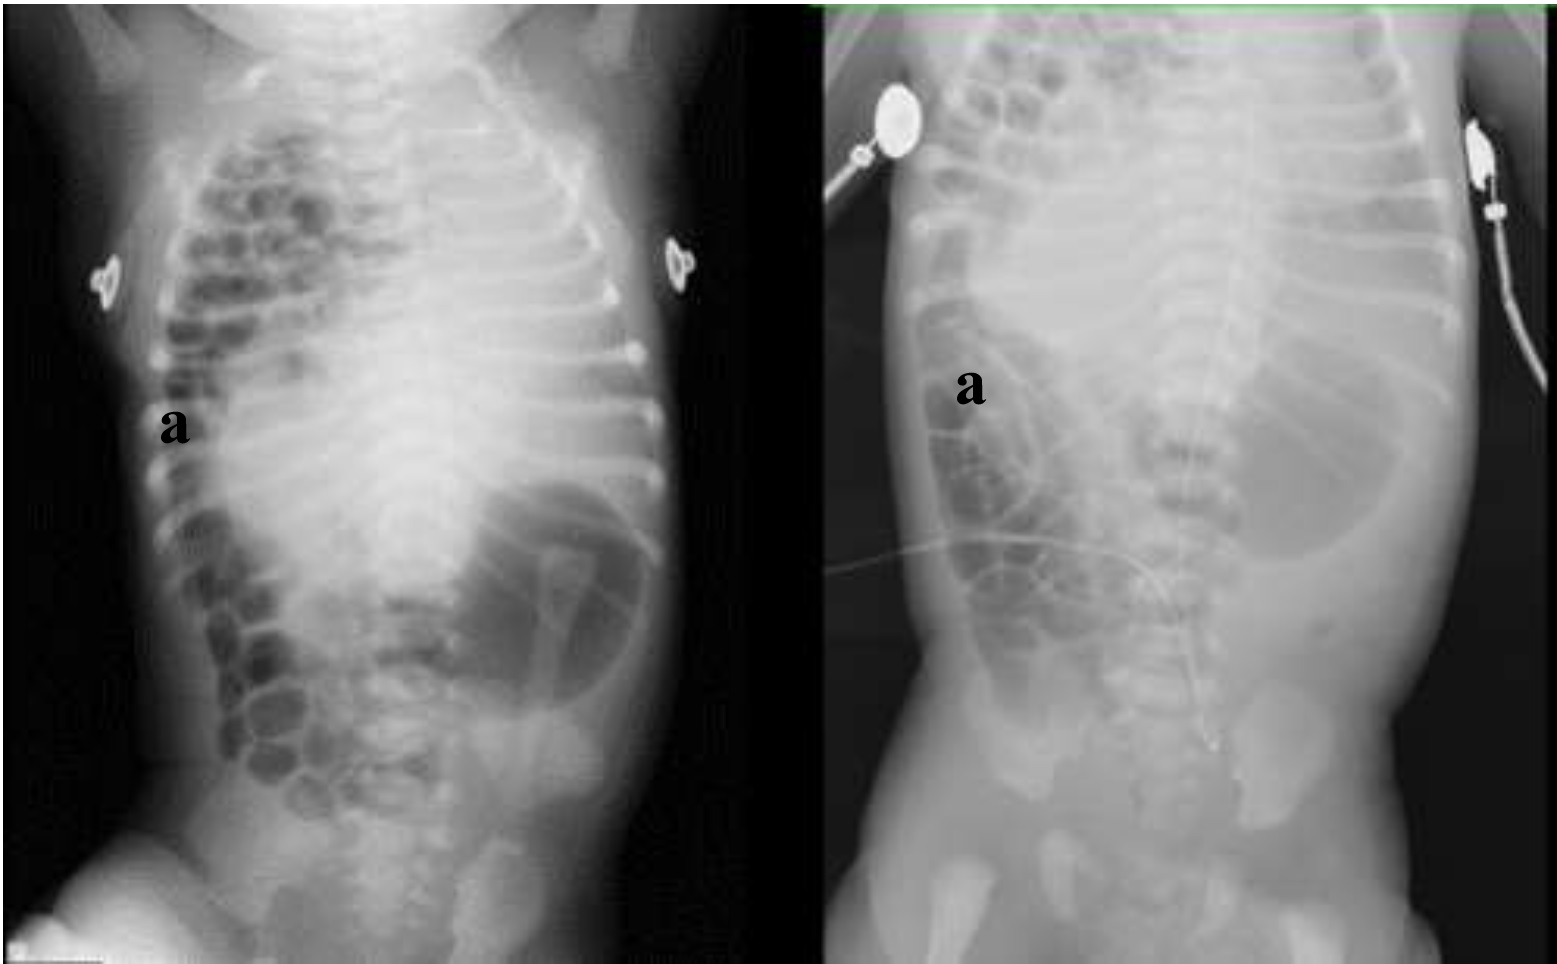

El “Tumor de Wilms; Reporte de un caso”.

"Nefroblastoma; Reporte de un caso".

Kassandra Aglae Salazar Vázquez, Yanyn Cabrera, Dr. Arturo Garza, Dra. Verónica Rodríguez, Dra. Rosario Medellín, Dr. Marco Ponce

e421

Hernia diafragmática congénita derecha: reporte de un caso exitoso tratado por toracoscopia.

Luis Alejandro Garcia Rairan, Angelica Cruz, Alejandra Alfonso, Cristina Angulo, Sebastian Silva, Andres Delgado

e438

Enterocolitis necrotizante en un recién nacido a término hijo de madre con VIH, atendido en unidad de cuidado intensivo neonatal, de un hospital de tercer nivel en el Departamento del Tolima, Colombia

Martha Letty Arias Penagos, Jose David Gomez Vasco, Iván Alejandro Villalobos

e449